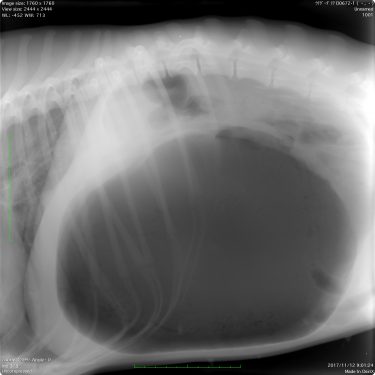

アイリッシュウルフハウンドの胃拡張・捻転症候群

| 症状 | 今朝、急に体調が悪化した。お腹がパンパンに膨らんでいる |

問診の時点で胃拡張・捻転症候群が強く疑われたため、診断のためのレントゲン検査を行った。

胃は非常に重度に拡張・捻転しており、呼吸も弱くなっていた。

緊急対応として胃を穿刺し、抜気した。

抜気後、やや胃が縮小した